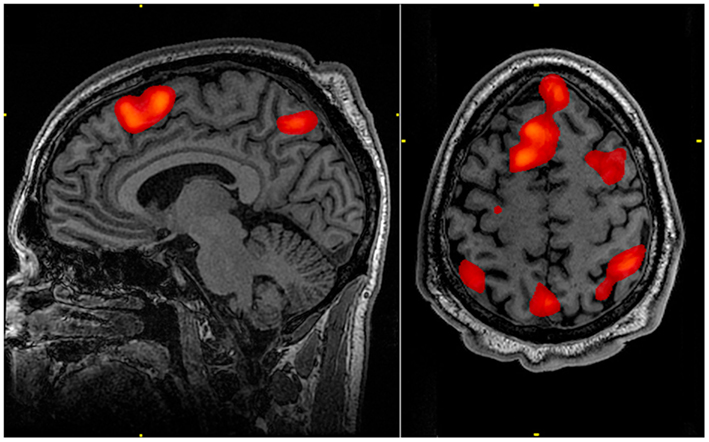

The Physiological Aspects of Psychology segment of this module strives to explain the biological mechanisms that underlie behavior. These physiological and anatomical foundations are the basis for many areas of psychology. In this chapter, you will learn how genetics influence both physiological and psychological traits. You will become familiar with the structure and function of the nervous system. And, finally, you will learn how the nervous system interacts with the endocrine system.

The States of Consciousness segment of this module will discuss states of consciousness with a particular emphasis on sleep. The different stages of sleep will be identified, and sleep disorders will be described. The chapter will close with discussions of altered states of consciousness produced by psychoactive drugs, hypnosis, and meditation. (Image Credit: Public Domain, Wikimedia)Upon completion of this module, you will be able to:- Discuss how gene-environment interactions are critical for the expression of physical and psychological characteristics